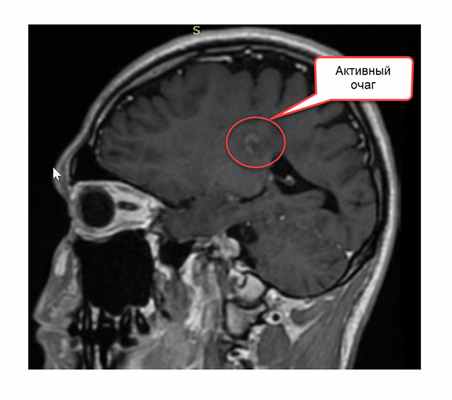

Наконец необходимо уточнить, что такое контрастное вещество. Это раствор, содержащий атомы гадолиния – металла, обладающего определенными магнитными свойствами. При его введении внутривенно, атомы металла проникают по кровяному руслу в сосуды головного мозга. Если очаг демиелинизации только появился, если в нем происходит воспаление, то мелкие сосуды, находящиеся в очаги проницаемы – у них не функционирует гематоэнцефалический барьер. И тогда в этот очаг начинают проникать атомы гадолиния, а в другие (старые) очаги не проникают, так как в сосудах старых очагов гематоэнцефалический барьер уже восстановился. На Т1-изображении зоны, где скапливаются атомы гадолиния, приобретают белый цвет, тогда мы говорим, что на изображении есть активные очаги.

- очаг на Т2-изображении, накапливающий контраст на Т1-изображении

- выявление при одном исследовании очагов накапливающих и не накапливающих контраст